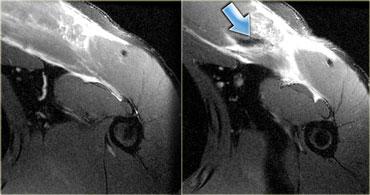

Bên trái là hình ảnh căng cơ với rách một phần cơ dưới vai.

Cơ dưới vai là cơ hội tụ (giống như cơ ngực chẳng hạn) với nhiều gân.

Phù nề sẽ có dạng phân bố đa lông chim, khi phù nề lan theo nhiều hướng dọc theo các gân khác nhau.

Ở ngoài cùng bên trái là hình ảnh rách hoàn toàn đầu gián tiếp của cơ thẳng đùi (mũi tên vàng).

Vết rách này xuất phát từ khớp háng.

Hình ảnh bên cạnh, cũng đã được trình bày ở trên, cho thấy một phát hiện hoàn toàn khác.

Có phù nề bao quanh gân xa kết nối với xương bánh chè.

Gân còn lại hoàn toàn bình thường (mũi tên xanh).